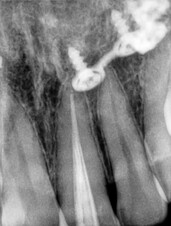

돌출된 앞니는 예방적 신경치료

돌출된 앞니 한 개는 예방적 신경치료를 해 줍니다. 그래야 치아에 통증이 없으며, 향후 치아뿌리에 염증 가능성을 피해 줍니다.

앞니에 신경치료를 할 때 주의해야 하는 부분이 있습니다. 그것은 앞니 신경치료후 변색입니다. 신경치료시 사용하는 특정 재료로 인해 치아변색이 서서히 올 수 있으니 주의가 요망됩니다. 변색이 되지 않는 재료를 꼭 써야 합니다!

치아삭제량 확인

해당 사례를 치료하는 과정입니다. 심하게 돌출되어 있던 앞니를 안으로 넣기 위해 충분한 삭제가 필요했고 그래서 해당 치아는 충분히 삭제 후 크라운으로 치료를 합니다.

돌출이 심한 치아를 주변치아 정도의 위치까지 삭제하게 되면 치아법랑질은 모두 사라지게 됩니다. 그렇기 때문에 법랑질에 강력하게 부착해서 치아와 한몸이 되는 라미네이트 치료를 돌출된 치아에는 할 수 없는 것입니다. 법랑질이 충분하지 않은 부분에 라미네이트로 만들어 앞에만 붙이면 금새 떨어지게 되기 때문입니다.